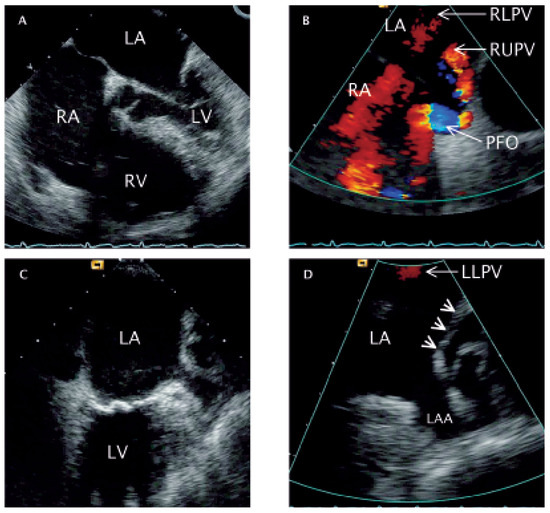

Anomalous Left Upper Pulmonary Vein Connection with Right Heart Failure Following Closure of Patent Foramen Ovale

by Christina Eigenmann and Christian Seiler

A68-year-old woman was admitted for rapidly progressive systemic sclerosis [...] Full article

Figure 1